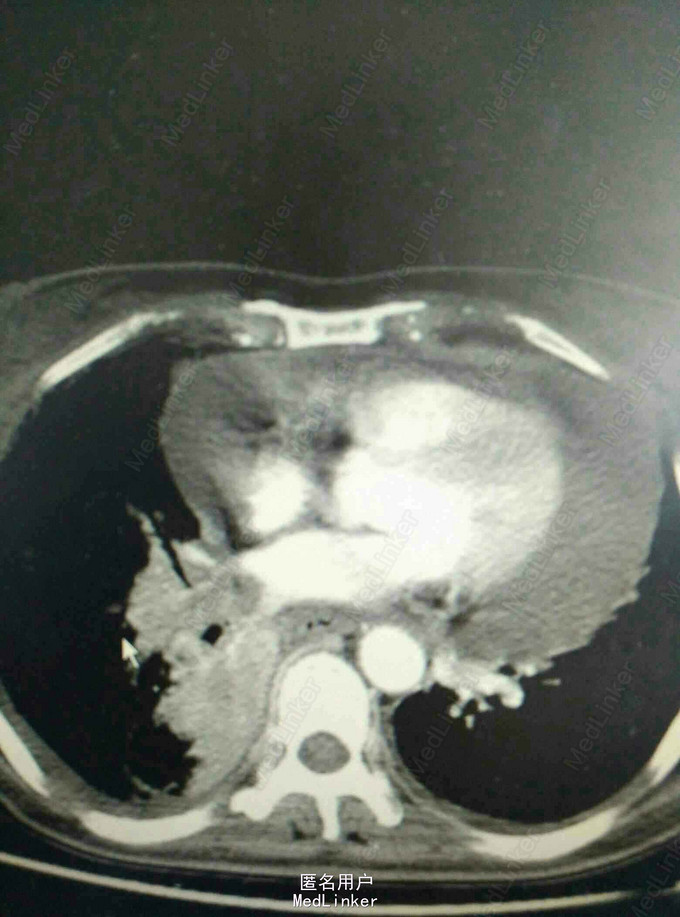

患者,女性,52岁。 2015年3月 因右侧胸腔积液,至外院就诊,胸水中找到腺癌细胞,胸部CT见右下肺占位。后多次胸腔闭式引流,但效果差。期间胸水脱落细胞检测EGFR,有突变,故口服靶向药物,并国产培美化疗一次。最近又出现心包积液,致呼吸困难入院。

入院后予以胸水引流,复查ct,行心包穿刺引流,改善症状,加强营养,纠正低蛋白。情况稳定后,在全麻下行右侧胸腔持续热灌注化疗,术中胸腔镜见胸壁大量转移病灶,取部分组织送检EGFR。术后经密切观察治疗,度过热疗损伤急性期。症情平稳后出院。术后EGFR阴性。